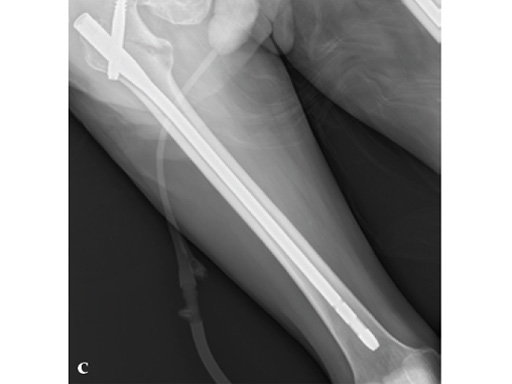

72-year-old female who sustained a closed intertrochanteric fracture in a car accident. The fracture was classified as an 31-A3-1. There were no other injuries reported.

Case provided by Cliff Turen, Macon, USA